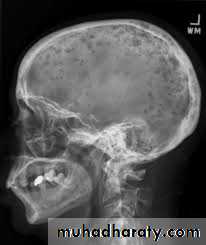

The malignant cell proliferation cause bone resorption that appear radiographically as a radiolucent punched out lesions and replace bone marrow leading to anemia , leucopenia , thrombopenia.